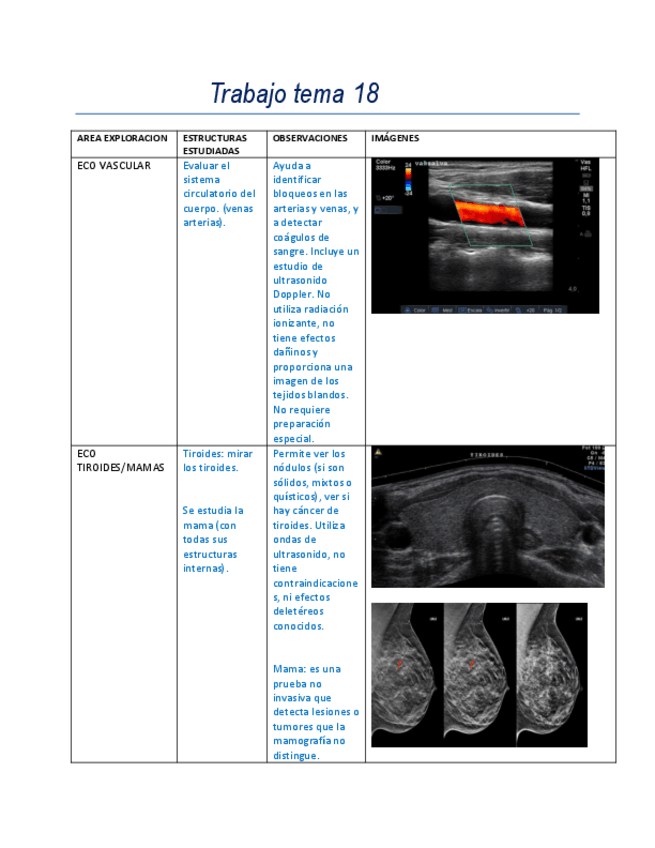

Apuntes - ECOGRAFIA.pdf